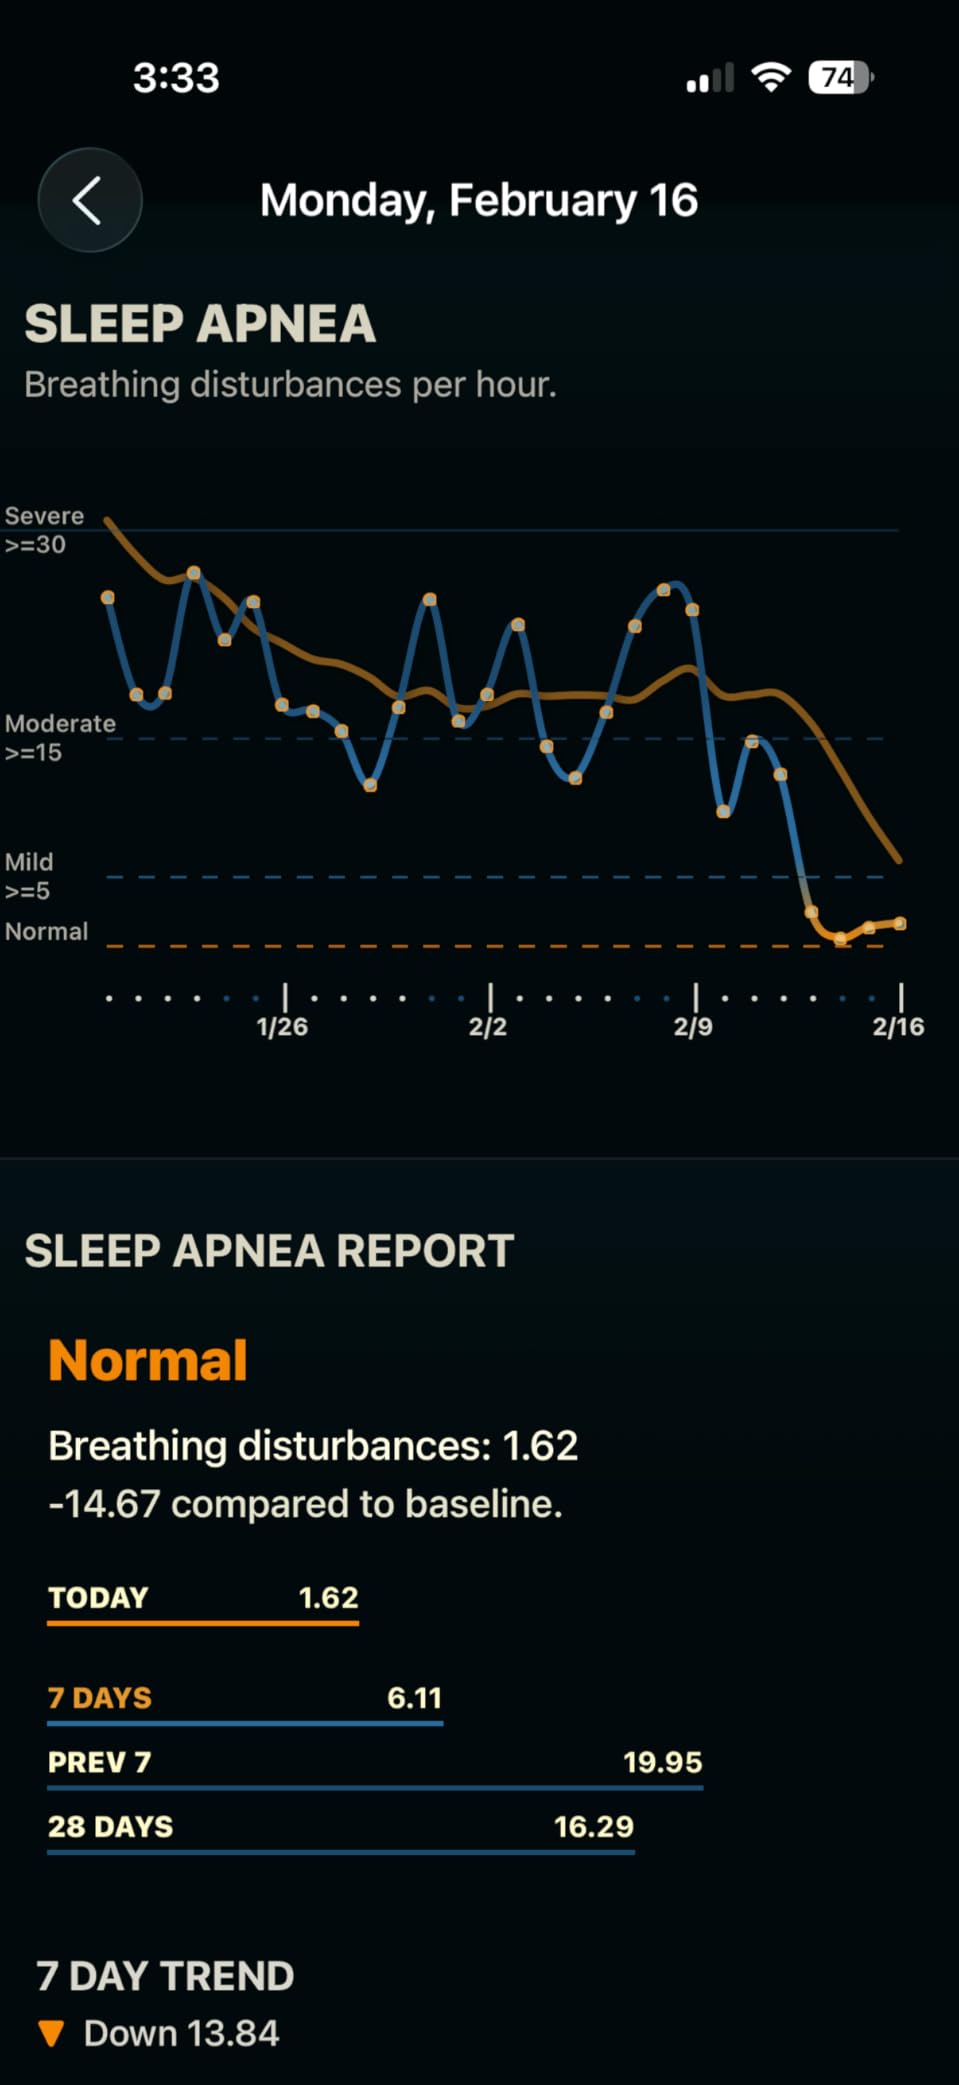

Sleep Apnea Warning: When to See a Doctor

Snoring can be a symptom of obstructive sleep apnea, a serious condition where your breathing repeatedly stops and starts during sleep. If you experience any of these warning signs, consult a healthcare professional before trying anti-snoring devices:

Gasping or choking during sleep, excessive daytime sleepiness despite adequate sleep time, morning headaches, difficulty concentrating, or a partner observing that you stop breathing during sleep. Sleep apnea requires medical diagnosis and may need treatment beyond over-the-counter devices.

Even if you don't have sleep apnea symptoms, if snoring persists despite trying multiple devices, a sleep study can identify underlying causes and guide more effective treatment options.